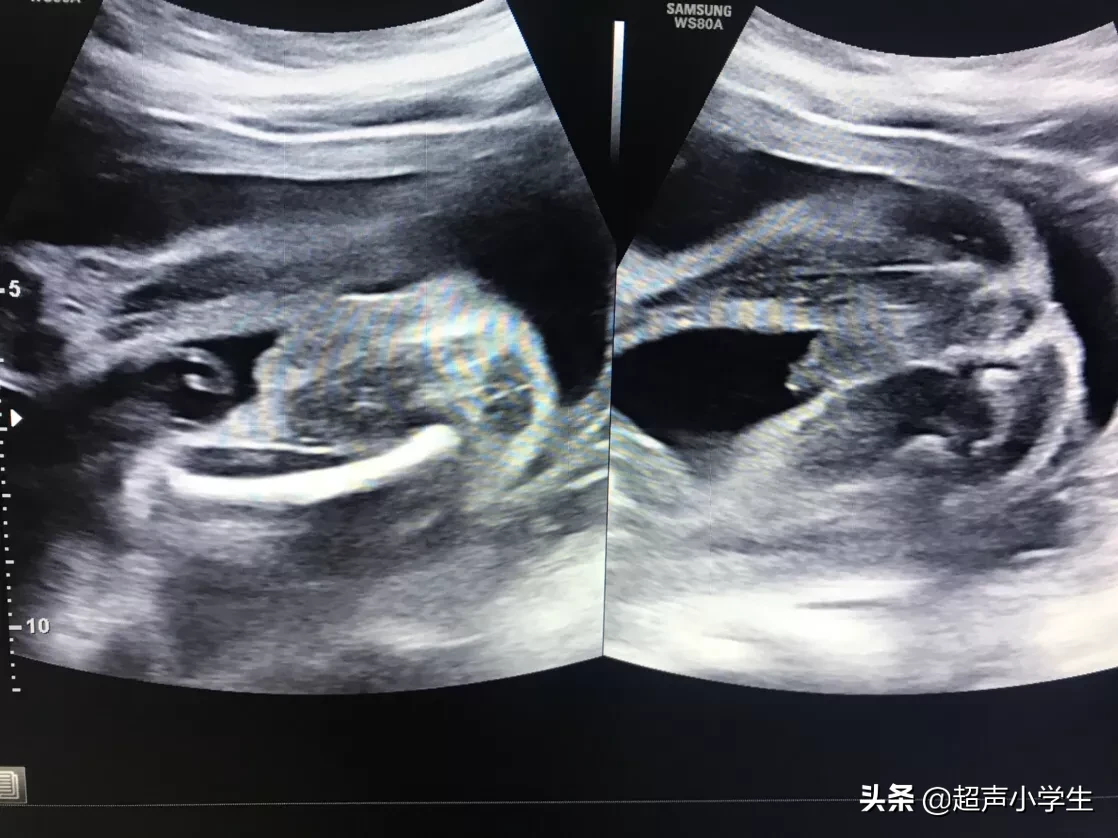

其实每一次测胎心率 , 结果都会不一样 。偶尔高很多 , 或者低很多都是正常的现象 。

多次产检胎心率都在固定的一个范围:我家男宝胎心率基本固定在140~145之间 , 而我家女宝胎心率基本固定在149~155之间 。通常我家女宝的胎心率会更高一些 。

孕晚期的胎心率比较稳定:怀孕晚期 , 基本测胎心率的次数比较多 , 而且宝宝发育相对成熟 , 相比孕早中期 , 胎心率要稳定一些 。我家男宝在孕早期胎心率有超过150次/分 , 而我家女宝在孕早中期胎心率也有低于140次/分的时候 。生男孩胎心率每个人是不一样的:我和我闺蜜一起去做产检 , 她宝宝胎心率普遍比我家男孩高 , 而且多在150次/分以上 , 我一直以为她很有可能怀的是女宝 , 而宝宝出生 , 一样是男孩 。